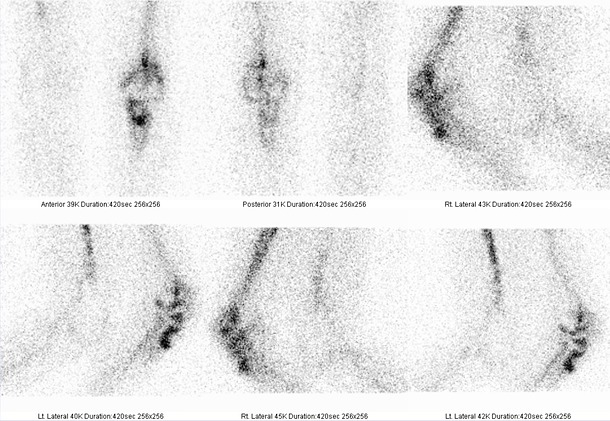

K odlišení toho, zda se jedná o prosté uvolnění TEP nebo o uvolnění zánětlivé, jsme za šestnáct dní po scintigrafii skeletu pacienta vyšetřili znovu. I.v. jsme aplikovali 700 MBq

99mTc značených monoklonálních protilátek proti granulocytům. Celotělovou a cílenou statickou scintigrafii kolenou a přilehlých částí bérců a stehen jsme provedli za 4 hodiny po podání tohoto radiofarmaka opět na dvouhlavé tomografické scintilační kameře E.CAM firmy Siemens. Pozorujeme zvýšenou depozici radioindikátoru v oblasti pravého kolena a to jak kolem femorální, tak kolem tibiální komponenty totální endoprotézy. Nález svědčí pro zánětlivé ložisko v oblasti pravého kolena v okolí tibiální a femorální komponenty TEP

(obr. 5, 6 ). V mediálním kondylu pravé tibie zvýšená depozice značených protilátek proti granulocytům není patrná, je zde tedy podle scintigrafie skeletu jen vyšší perfuze a osteoblastická aktivita, která je nejspíše podmíněná degenerativními změnami.

/ Obr. č. 5: Celotělová scintigrafie zánětu za 4 hod. po aplikaci značených monoklonálních protilátek proti granulocytům, projekce přední a zadní /

/ Obr. č. 6: Statická scintigrafie zánětu za 4 hod. po aplikaci značených monoklonálních protilátek proti granulocytům, projekce přední, zadní a 2x obě boční- scintigrafie obou kolenou /